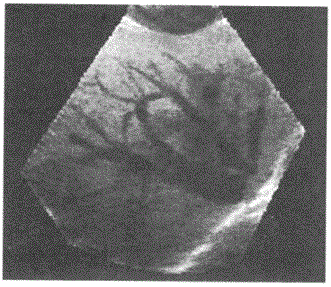

问题 下图是采用了哪项超声新技术显示肝脏及其内部血管:

选项 A.血管造影成像 B.血流能量图模式三维成像 C.表面模式三维成像 D.透明模式三维成像

答案 D